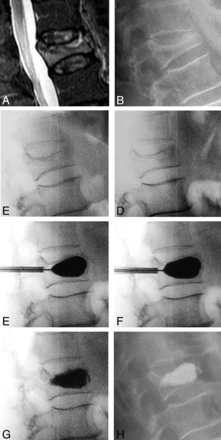

Figure 5 is an illustrative case example depicting angular-deformity correction for the treated fracture at all stages of the kyphoplasty procedure. The case example is from a 72-year-old female patient with a mobile L1 fracture. Placing the patient prone on the operating table resulted in an 8.9° correction without bolsters and an additional degree of correction after placing chest and hip bolsters. The patient was randomized to the IBTF group, and the first balloon inflation was uniform, providing an additional 7° of angular-deformity correction; the IBT inflation pressures were 120 PSI (bilateral) and were 4.0 (right) and 4.2 (left) mL in volume. After curette use and a second balloon inflation, there was a better inflation pattern and volume, with an additional degree of angular-deformity correction; for the second inflation, pressures were 106 (right) and 120 (left) PSI with an inflation volume of 5.0 mL for each side. The overall postoperative kyphosis correction of the fracture was 12.4°, and the local Cobb angle correction was 9.1°. In the overall cohort, 57 of 112 patients (51%) had fractures with dynamic mobility (Table 2); we performed analyses comparing mobile versus nonmobile fractures. The median age for mobile fractures was statistically significantly lower (3.0 weeks; IQR, 2.0–6.0 weeks) than nonmobile fractures (6.0 weeks; IQR, 3.0–10.0 weeks; P = .042).

Case illustration of kyphosis correction for each step in the kyphoplasty procedure. A, Preoperative T2 short-τ inversion recovery MR imaging. B, Preoperative standing x-ray. C, Intraoperative postural reduction without bolsters. D, Intraoperative postural reduction with a bolster. E, Intraoperative first balloon inflation. F, Intraoperative curette and second balloon inflation. G, Intraoperative cement placement. H, Postoperative standing x-ray.